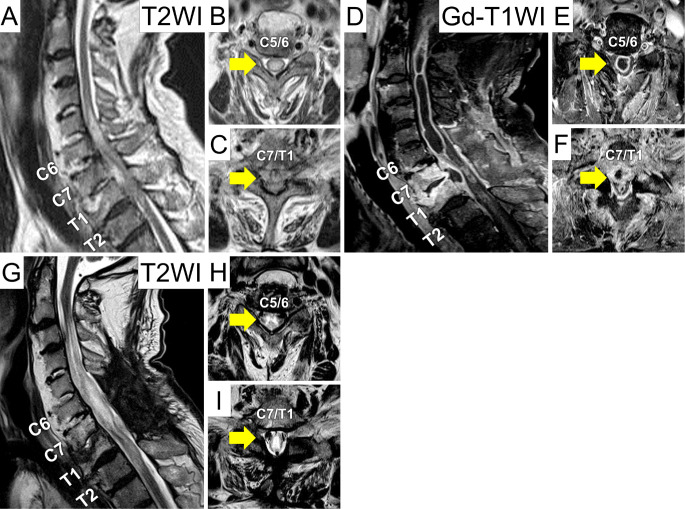

Intramedullary Spinal Cord Abscess due to Traumatic Esophageal Perforation Associated with Cervicothoracic Anterior Osteophytes: A Case Report.